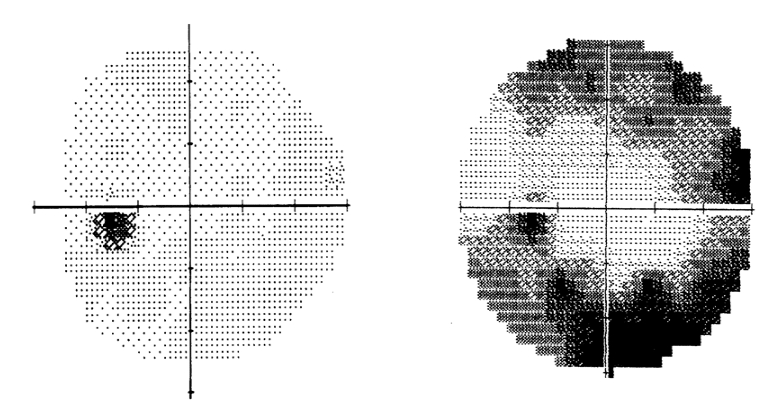

▶ 시야검사 : 시야의 손상 여부를 확인하기 위한 검사로 녹내장으로 진단이 되면 이후에 정기적으로 실시하게 됩니다. 어두운 암실에서 이마와 턱을 고정한 상태로 정면의 한 점을 보고 있다가 작은 빛이 불규칙적으로 여기저기 눈 앞에 나타나면 빛을 보았다고 생각되었을 때 버튼을 누르면 되는 검사입니다. 이때 눈을 움직이지 않은 채 검사를 진행해야 하는데 본능적으로 눈이 움직이다 보니 검사시간이 오래 걸리기도 합니다.